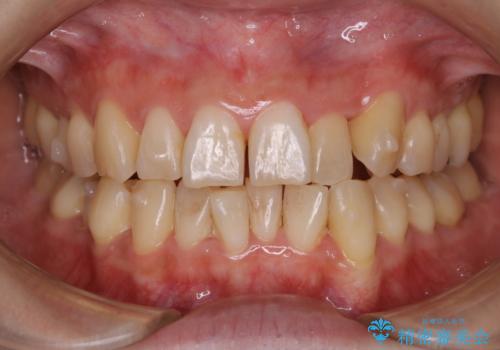

大好きなブラックコーヒーによる歯の着色を綺麗にしたい